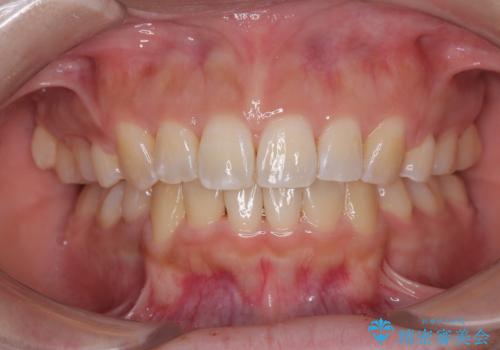

マウスピース矯正が煩わしい ワイヤー装置での非抜歯矯正

担当医 藤巻太一朗